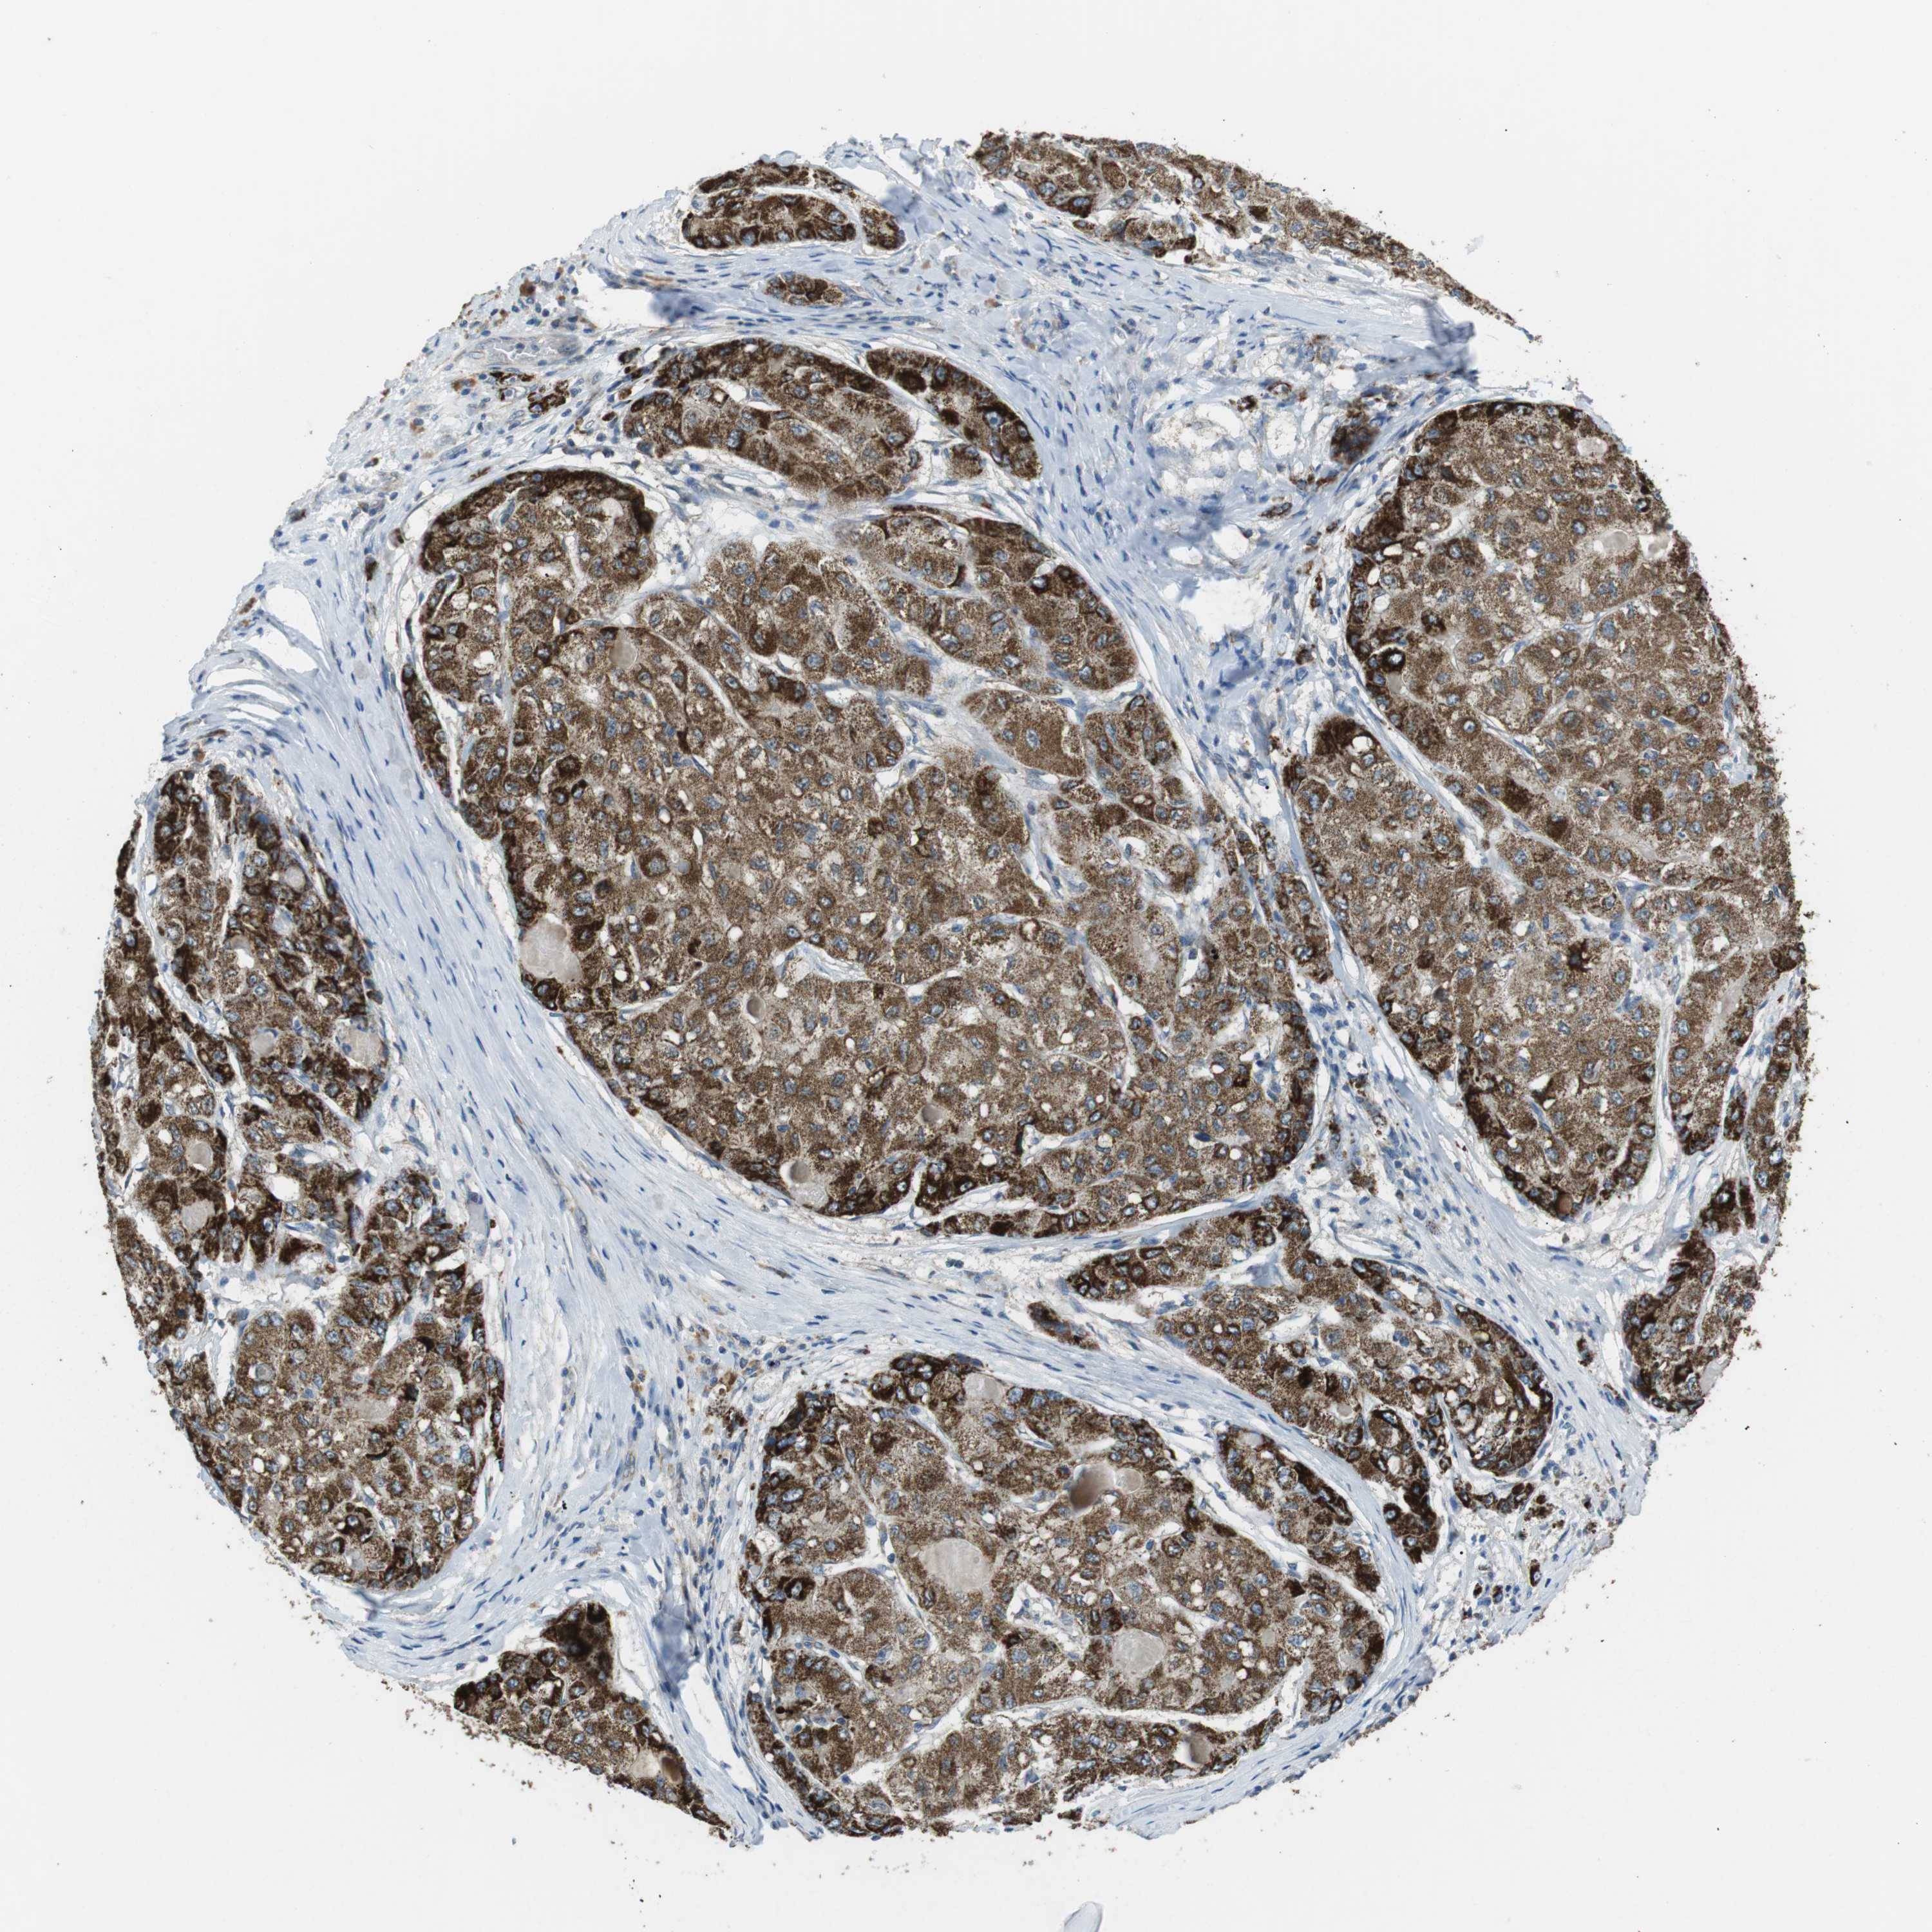

LIVER CANCER - Protein expressioni

A mouse-over function shows sample information and annotation data. Click on an image to view it in a full screen mode. Samples can be filtered based on level of antibody staining by selecting one or several of the following categories: high, medium, low and not detected. The assay and annotation is described here.

Note that samples used for immunohistochemistry by the Human Protein Atlas do not correspond to samples in the TCGA dataset.

Antibody stainingi

Antibody staining in the annotated cell types in the current human tissue is reported as not detected, low, medium, or high, based on conventional immunohistochemistry profiling in selected tissues. This score is based on the combination of the staining intensity and fraction of stained cells.

Each image is clickable and will lead to virtual microscopy that enables deeper exploration of all samples and also displays staining intensity scores, fraction scores and subcellular localization as well as patient and tissue information for each sample.

Antibody CAB016358

Staining

High

Medium

Low

Not detected

Intensity

Strong

Moderate

Weak

Negative

Quantity

>75%

75%-25%

<25%

None

Location

Nuclear

Cytoplasmic/membranous

Cytoplasmic/membranous,nuclear

Cholangiocarcinoma

Carcinoma, Hepatocellular, NOS